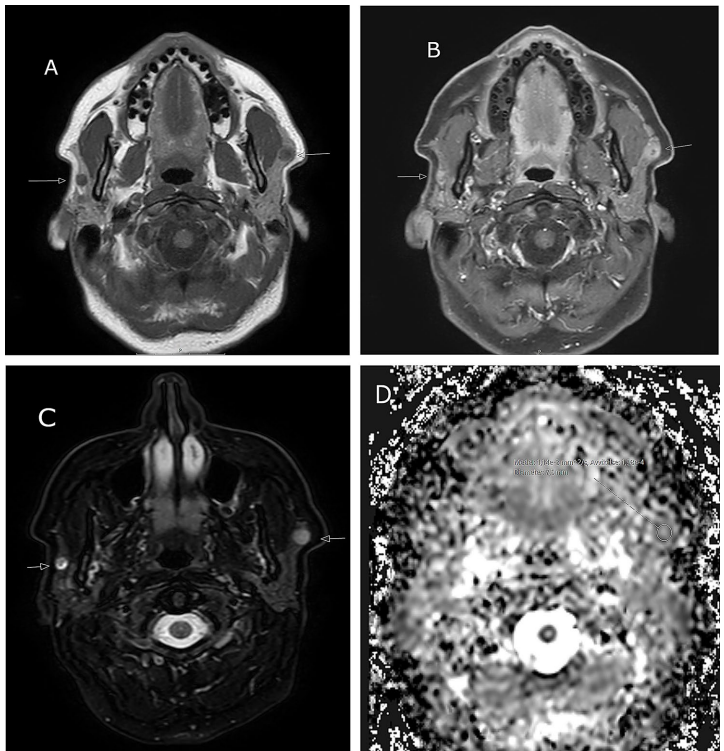

患者1:MRI显示右侧病灶T2W低信号(ADC=1.1×10-3

mm2

/s)提示恶性,左侧混合信号(ADC=1.4×10-3

/s)倾向良性。术后病理证实为SDC(pT4N2)与PA的罕见组合。

该研究首次系统阐述了双侧唾液腺肿瘤的"诊断-治疗-预后"全流程管理策略,其提出的"镜像评估"理念已被纳入瑞典头颈肿瘤诊疗指南。对于占位病变性质判读,作者强调ADC值截点1.2×10-3

/s具有重要鉴别价值——低于该阈值提示恶性可能,这一发现为无创诊断提供了量化标准。